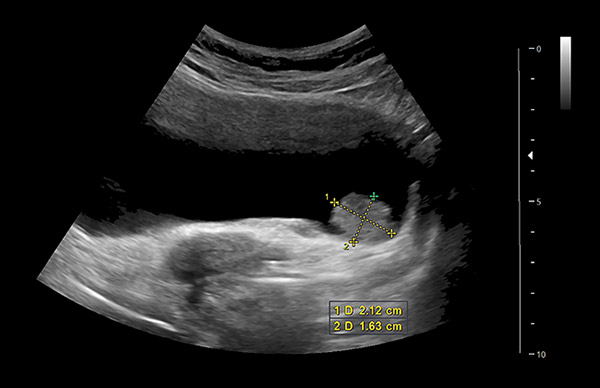

11. kép:

Hólyagtumor

Ezen a képen egy hugyhólyag falából kiinduló daganat látható. Itt egy karfiol szerű kinövés látható a hugyhólyag alsó falán, ami a képen a lemért képletnek felel meg.